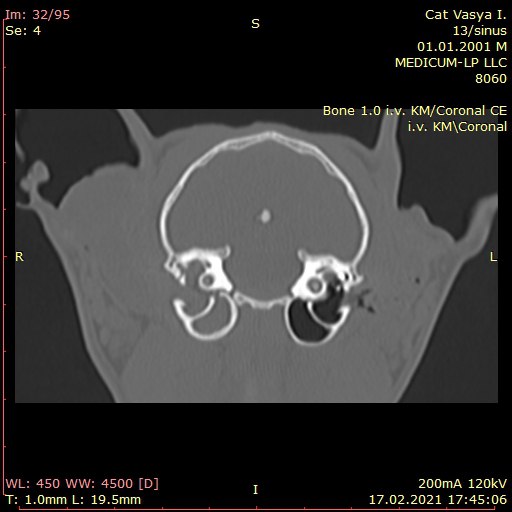

КОМП'ЮТЕРНА ТОМОГРАФІЯ - метод, заснований на отриманні пошарового рентгенівського зображення.

Тому, ми отримуємо можливість точно встановити локалізацію та поширеність патологічного процесу, а також оцінити результат лікування.